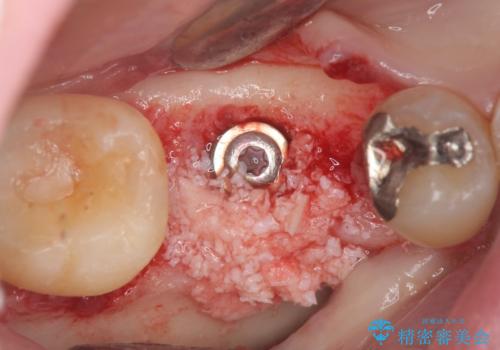

- 44万円(ストローマンインプラント・チタンカスタムアバットメント・仮歯・ジルコニアクラウン)費用は治療当時の料金となります

虫歯の放置により吸収してしまった骨も造成を行うことでインプラント周囲環境をしっかりと整えています。